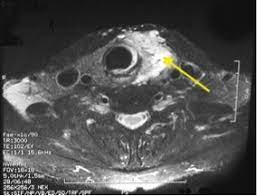

Doctors often use them to guide a needle during a biopsy. Your doctor will often use an ultrasound to create images of a fetus during pregnancy. Within the first two days of the patient's arrival at our hospital. If the fna shows cancer, the pathologist (the doctor examining the samples) can often tell what type of cancer it is. In most cases, throat cancer originates in the flat cells that line the inside of the throat, a muscular tube that extends from the nose to the bottom of the neck. And if this isn't cancer, could anybody offer an explanation as to what would cause a sore throat and growing lump? Similar to other types of ct scans, a throat ct scan involves the administration of radiation, which can increase one's risk for cancer over the. They might take images of your thyroid with an mri, ct scan, or ultrasound. Ductal carcinoma in situ is usually seen as linear microcalcifications (see arrows), which demonstrate linear orientation, as seen in this patient. Throat cancer can develop in any part of the throat. Cervical cancer requires specialized care. A small device called a transducer is moved over the area. Throat cancer is a condition that is characterized by the development of malignant tumors in the throat (pharynx), voice box (larynx) or tonsils.

Your voice box sits just below your throat and also is susceptible to throat cancer. The symptoms and appearance of throat cancer depend on the specific part of the throat that is affected and the stages of its development. Throat cancer most often begins in the flat cells that line the inside of your throat. Ultrasound imaging can help determine the composition of lump, distinguishing between a cyst and a tumour. Ultrasounds are usually quick and most don't require special preparation. Throat cancer is a malignancy of either the tonsils, pharynx, or larynx. Your doctor will often use an ultrasound to create images of a fetus during pregnancy. Thyroid nodules are lumps that can appear in the thyroid gland in front of the throat. The ultrasound images are then projected onto a computer screen. A primary cancer of the lymphatic system is called lymphoma. Or, you might be told that you don't have cancer, based on an ultrasound, when in fact you do. Needle biopsy is only indicated if there is a mass within the thyroid goiter which is suspicious for malignancy. It can detect abnormal tissues, growths, and cysts and give a suspicion of cancer based on how those images look.